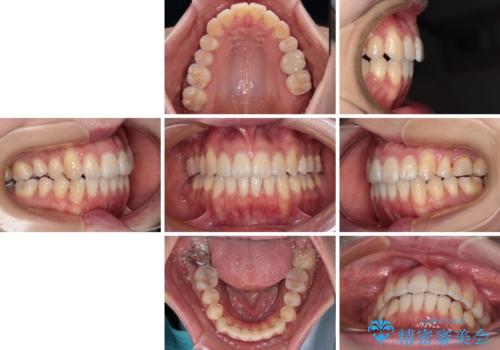

八重歯と開咬の抜歯矯正 ワイヤー装置を併用したインビザライン矯正治療

- 咬み合わない前歯と八重歯などのデコボコを気にして来院された患者様です。

上下前歯の位置を比較すると上顎が前方にあり、デコボコ改善でより上顎が前方に行く可能性があります。

開咬の改善にはインビザラインが有効であり、インビザライン単体での治療を検討しましたが、上顎前突を回避するために上顎左側第一小臼歯抜歯を行うこととしたため、補助装置とワイヤー矯正を併用した上で、インビザラインによる矯正治療を行うこととしました。

インビザライン矯正治療では、臼歯の圧下による前歯部の早期接触が大きな問題となっています。開咬では、その臼歯圧下を逆手にとって前歯部の非接触を改善させることができます。